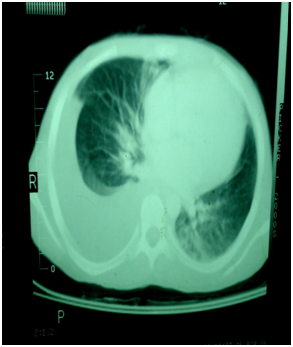

Laboratory Investigations (Table 1) revealed moderate normocytic normochromic anaemia with normal reticulocytic count: hypoalbuminemia with normal 24-hours protein collection in urine: raised acute phase reactants (Erythrocyte sedimentation rate "ESR" and C-reactive protein "CRP"): normal anti- nuclear antibody: anti double stranded DNA: rheumatoid factor and negative tuberculin test. Human immunodeficiency virus (HIV) serology was negative at presentation. Chest X-rayshowed moderate right sided pleural effusion. Computerized tomography (CT) neck: chest and abdomen showed multiple enlarged cervical lymph nodes 1.5*1cm: enlarged bilateral axillary lymph nodes the largest one 2*3cm: multiple enlarged anterior meditational lymph nodes 2.5*2.5cm: moderate right sided pleural effusion: left lower lung lobe pneumonic consolidation: mild hepatomegaly and moderate free ascitis (Figure 1). Exicisional biopsy of an axillary lymph node (Figure 2) was performed and histopathological examination revealed hyaline vascular Castleman's disease ( increased number of follicles with atrophic germinal centers and the inter follicular area showing proliferation of hyalinized capillaries and thick wall blood vessels).Child received adequate supportive care and CHOP regimen as a combination chemotherapy {cyclophosphamide 1000mg/m2 (d1): vincristine 1.5mg/m2 (d1): doxorubicin 40mg/m2 (d1): prednisolone 40mg\m2 (d1-d5)}. After 3 cycles of CHOP: there is marked clinical improvement with disappearance of constitutional manifestations: lower limb oedema: ascitis: pleural effusion and puffiness of the eyes.

Figure 1Radiological findings at presentation.

Figure 1a Chest X-ray showing moderate right sided pleural effusion.

Figure 1B Chest showing right sided pleural effusion.

Figure 1C CT abdomen showing moderate free ascitis.